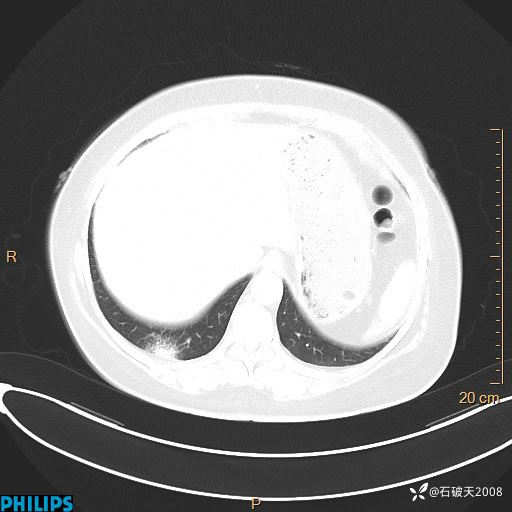

肺窗